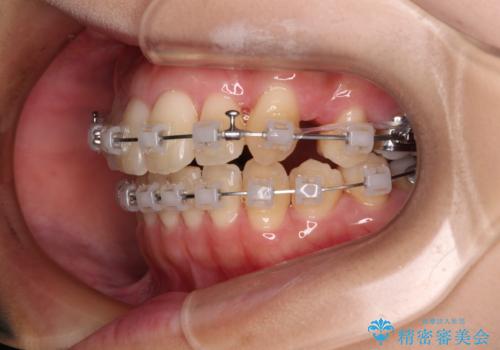

- クリアブラケット

- 1年11ヶ月

下顎歯列の叢生は軽度であることと、口元の突出感が全くなかったことから、八重歯解消のために上顎左右第一小臼歯を抜歯し、ワイヤー装置にて矯正治療を行うこととしました。

八重歯をスムーズに解消するために、補助装置を用いることで速やかに歯列を整えることができました。